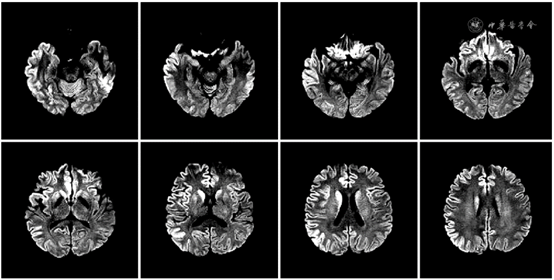

神经系统检查:无反应觉醒状态,不语,高级皮质功能检查不合作,颈强直,四肢肌张力高,双下肢腱反射(+++),右侧巴宾斯基征(+),余查体不配合。患者头颅DWI示高信号,呈“花边征”(见图2);

图2  2021年1月21日患者头颅MRI示双侧尾状核、壳核、大脑半球皮质多数DWI高信号,左侧丘脑枕稍增高,呈“花边征”